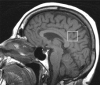

Figure 1

Placement of the 1H MRS voxel on a mid-sagittal T1 weighted image. The 8 cm3 (2×2×2cm) voxel is covering right and left hemispheric posterior cingulate gyri and inferior precunei.